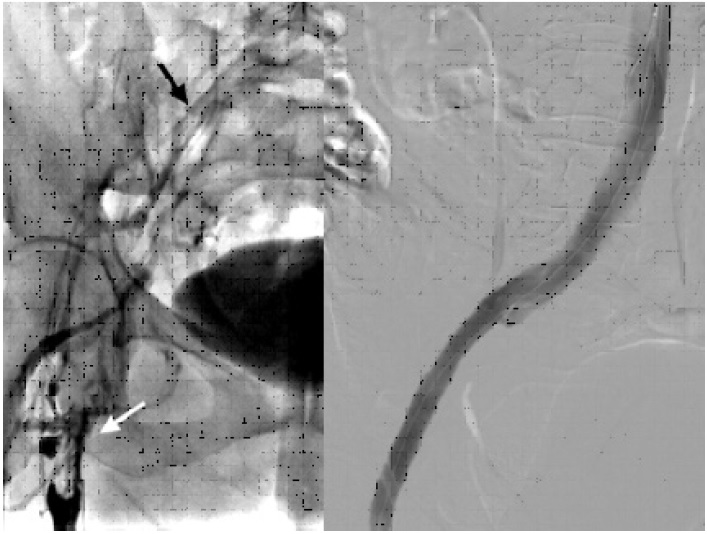

Se decidió llevar a la paciente a Hemodinamia para colocación de un filtro de vena cava inferior (VCI) por vía femoral derecha. Luego, con la paciente en decúbito ventral, se realizó una punción guiada por ecografía de la vena poplítea con colocación de un introductor 11 French por medio del cual se llevó a cabo una trombectomía mecánica de toda la oclusión con dispositivo Aspirex®S. Un claro sitio de compresión se notó al mismo nivel observado en la angiotomografía, que ocasionaba incluso una ruptura parcial de la vena con fuga de contraste sin descompensación hemodinámica. Se decidió colocar un stent venoso autoexpandible de 12 × 120 mm, y dilatación con balón, con un resultado final muy satisfactorio (Figura 2).

Imagen de estudio dividida en 2

Fig. 2 Izquierda. Flebografía inicial que muestra trombosis la desde vena femoral proximal (flecha blanca), que recanaliza con hipoflujo a nivel de vena ilíaca común (flecha negra). Derecha. Flebografía final post colocación de stent mostrando permeabilidad absoluta del eje ilíaco.